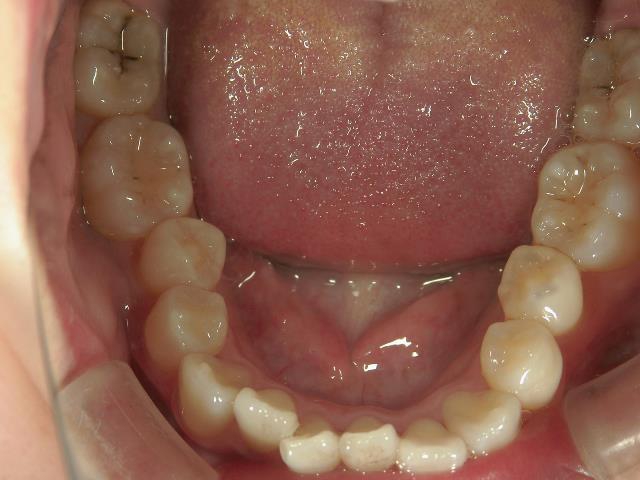

矯正歯科 治療後

矯正_灰色.pngno.8_8495_治療後_上.jpg矯正_灰色.png

no.8_8495_治療後_左.jpgno.8_8495_治療後_正面.jpgno.8_8495_治療後_右.jpg

矯正_灰色.pngno.8_8495_治療後_下.jpg矯正_灰色.png